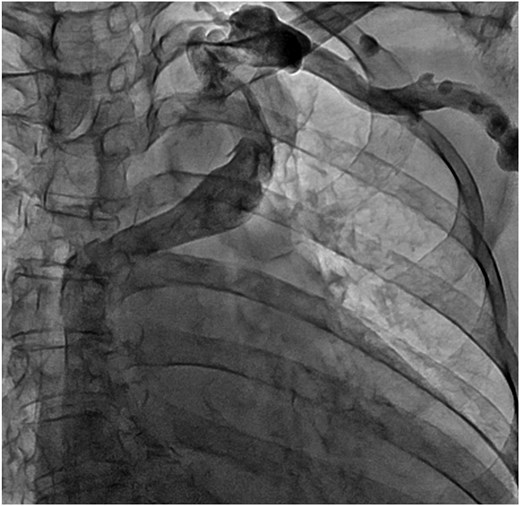

A 78-year-old woman with severe mitral regurgitation (MR), tricuspid regurgitation, and atrial fibrillation was admitted with worsening heart failure. She had hypertension, but no known CHD. She was 138 cm tall, weighing 34.6 kg, with a body mass index of 18.3 kg/m2. Her vital signs were normal. The N-terminal fragment of pro B-type natriuretic peptide was elevated at 2577 pg/mL. Chest radiography revealed cardiac enlargement and bilateral pulmonary edema. Transesophageal echocardiography (TEE) revealed shortening of the anterior and posterior leaflets of the mitral valve, with thickening of the commissure, indicating severe MR (Fig. 1 and Video 1). The tricuspid annulus diameter increased to 29.4 mm. No congenital heart diseases were detected. Contrast-enhanced computed tomography (CT) revealed that the left innominate vein coursed posterior to the ascending aorta, the so-called ALBCV, and joined the superior vena cava (SVC) 3 cm from the right atrium (Fig. 2 and Video 2). Venography of the left upper limb confirmed the ALBCV (Fig. 3 and Video 3). No communication existed between the ALBCV and the coronary sinus.

Venography of the left upper limb. The ALBCV joined the SVC, and no communication was observed between the ALBCV and coronary sinus.